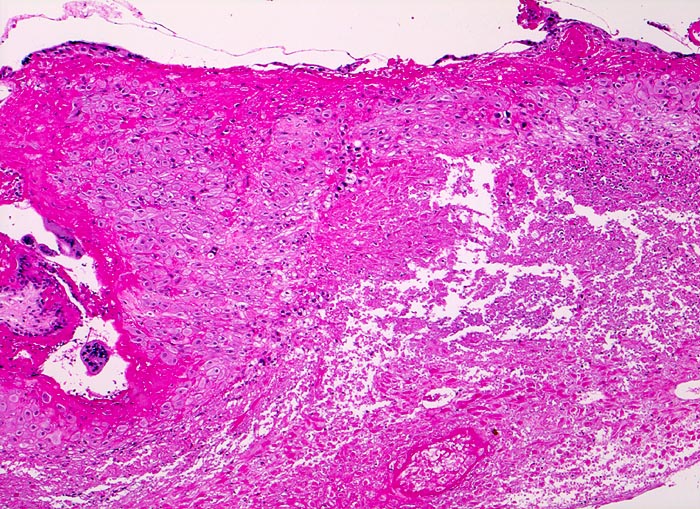

• Vorwiegend einschichtiges Zytotrophoblastepithel ohne Atypien und mehrkerniger Synzytiotrophoblast. Physiologische polare Trophoblastproliferate.

• Schwangerschaftsendometrium mit hypersekretorischen sägezahnförmigen Drüsen und bizarren Kernatypien (Arias Stella Phänomen).